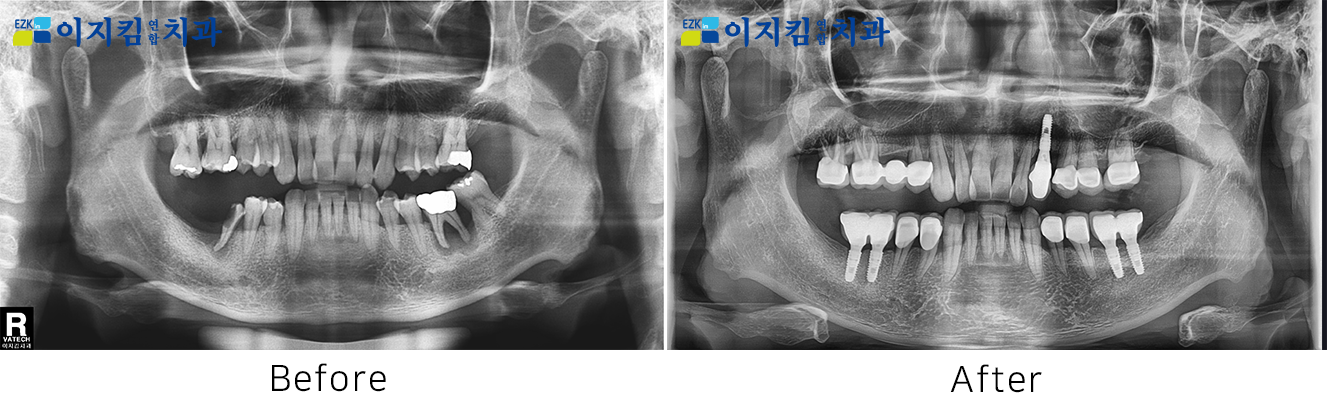

ÀÓÇöõÆ® Àü ¡¤ ÈÄ »çÁø

[

Á¶È¸¼ö : 2842

]